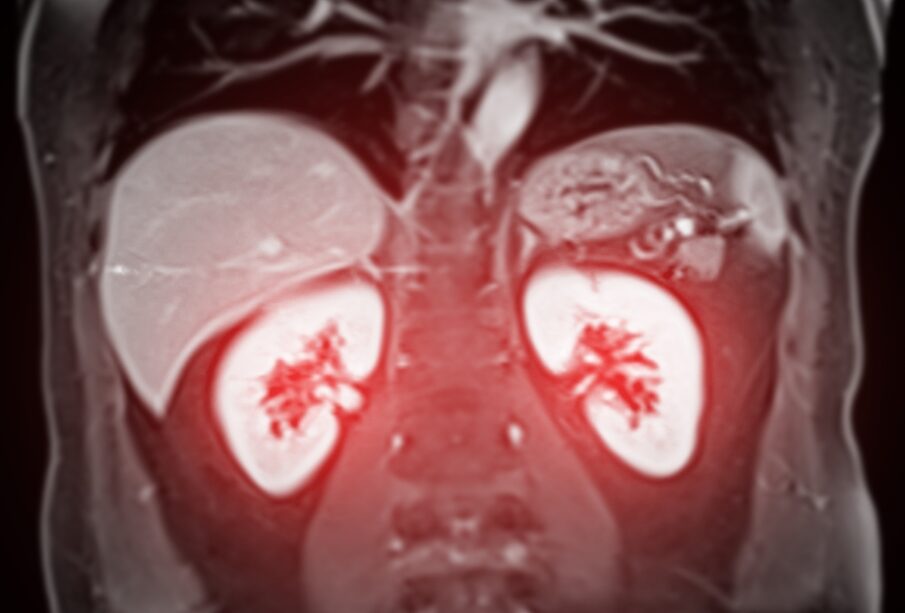

Vaizdo diagnostika: pagrindiniai tyrimo metodai

- Magnetinis rezonansas (MRT). Ypač tinkamas vertinant minkštųjų audinių pokyčius arba jei kyla įtarimų, kad navikas auga į venas. Taip pat gali būti naudojamas, jei pacientas alergiškas kontrastui ar sutrikusi inkstų funkcija. Tačiau MRT neatliekamas, jei organizme yra metalinių implantų.